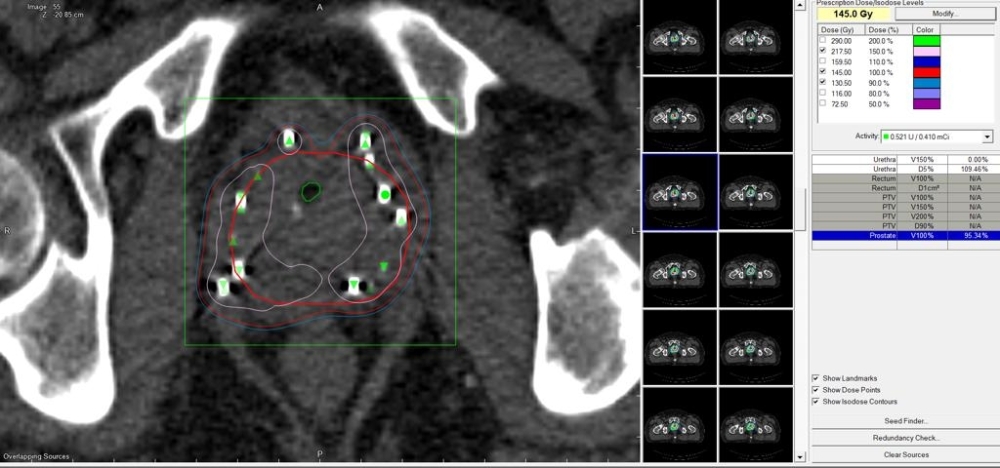

The operation was conducted by Dr Nadeem Pervis a senior consultant radiation oncologist, with a team of specialized doctors, medical physicists, anaesthetists, therapists and nurses. The operation was 2 hours long, where 82 radioactive seeds of Iodine 125 were implanted in and around the prostate.

The brachytherapy procedure involves insertion of needles containing radioactive seeds smaller than grains of rice, these seeds release radiation locally over a number of days, destroying the cancer cells stopping them from dividing and growing.